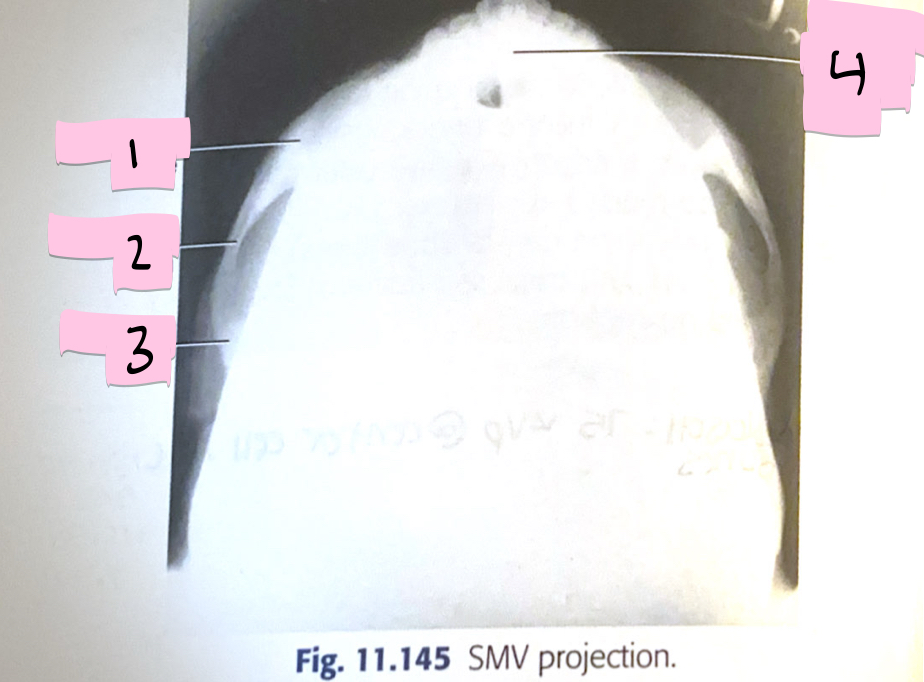

What is 1 pointing to?

Zygomatic bone

What is 2 pointing to?

Zygomatic arch

What is 3 pointing to?

Temporal bone

What is 4 pointing to?

Mandibular symphysis